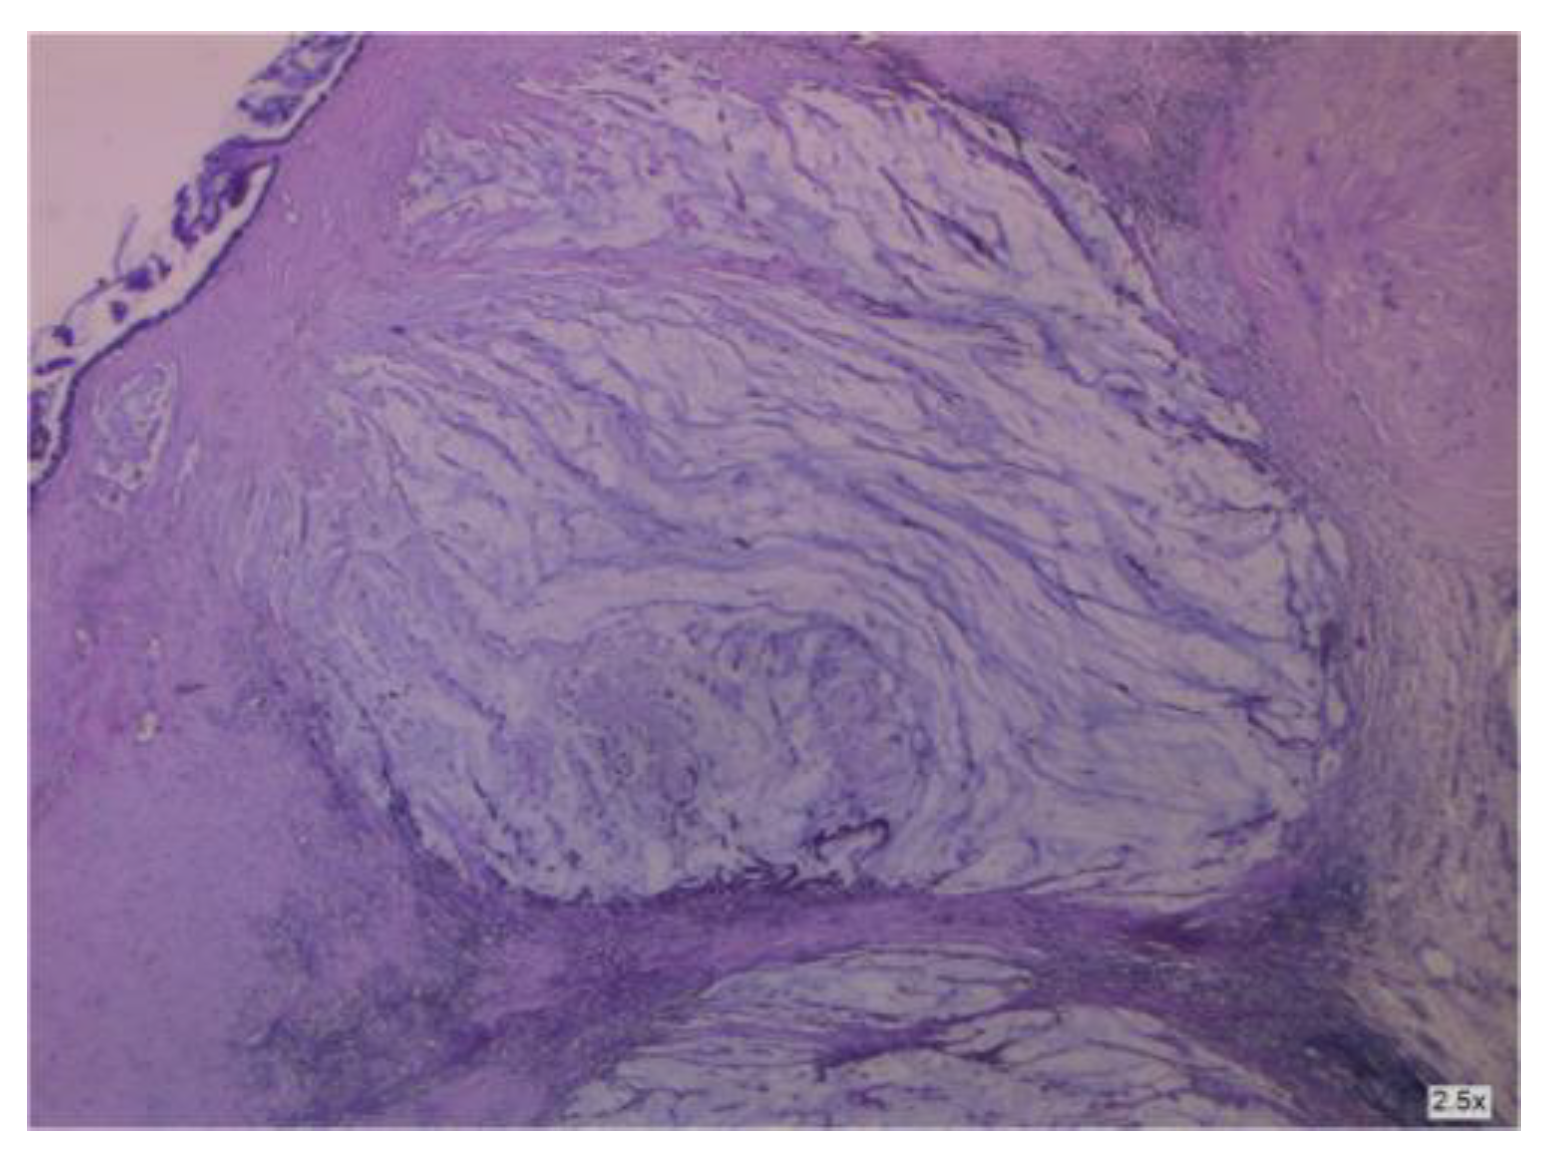

3.1.6. A Mucinous Borderline Tumor Developing inside an Ovarian Teratoma

3.2.2. Clinical and Pathology Findings